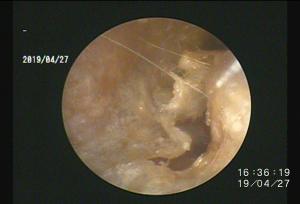

今回アップした動画は慢性外耳炎の中でも管理が困難な「耳垢腺過形成」による症例への治療動画になります

このような症例は管理が困難なため「全耳道切除」が一般的ですが、耳を摘出する手術は侵襲性が高いためなるべく避けたいところです。顔面神経麻痺などの副作用が懸念されます。

当院では内視鏡レーザー治療による緩和処置をすることで点耳薬による症状の改善を期待することができます

このような症例は案外多いため、一度精査を行い適切なケアをしてあげることがおすすめされます